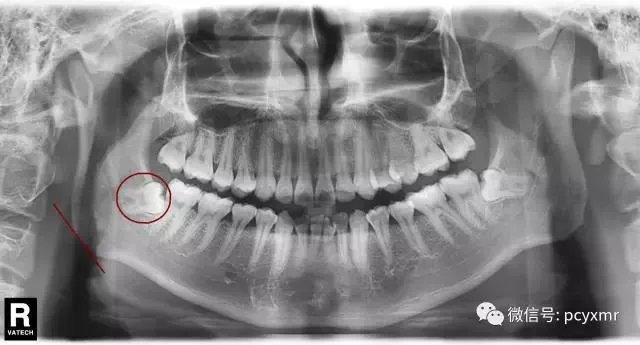

这是张面部正向的X光片,圈内为智齿所在区域。一般来说,即使要拔掉智齿,操作范围不会超过这个圈。划线处是下颌骨的外沿,这里的轮廓基本决定脸的轮廓,可以看到两个地方有一个距离。所以说拔智齿就能瘦脸是不科学的。